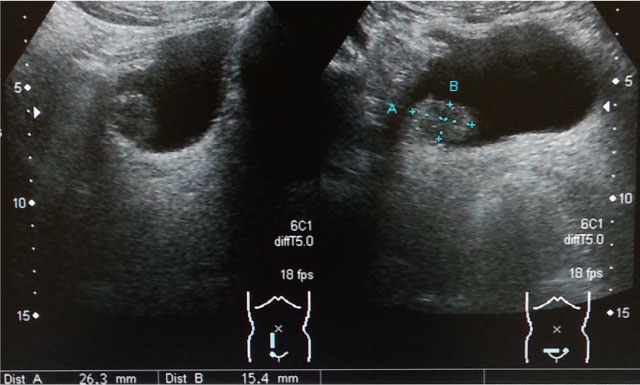

・腹部エコー:26.3mm x 15.4mmの膀胱腫瘍を認める。